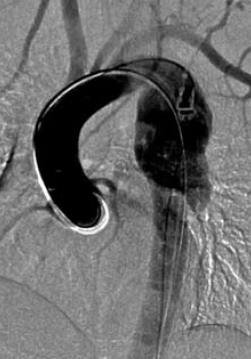

1. ábra.

Autóbalesetben sérült 26 éves ffi. DSA felvétele 3 héttel a baleset után. Az isthmicus szakaszon álaneurysma ábrázolódott.

1. 26 éves ffi autóbalesetben utasként szenvedett el mellkasi zúzódást, bordarepedést és tüdő contusiót. A kiszélesedett mediastinum és kis mennyiségű mellkasi folyadékgyülem vetette fel isthmicus tompa aortasérülés lehetőségét, amit DSA vizsgálattal igazoltunk. Hypotenziv kezelés mellett keringése stabil, a mediastinum kiszélesedése és haematologiai statusa nem változott. 3 héttel a sérülést követően bal oldali thoracotomia útján aorto-aorticus Dacron grafttal, mesterséges keringés alkalmazása nélkül, interpositiot végeztünk (1.,2.,3. ábra).